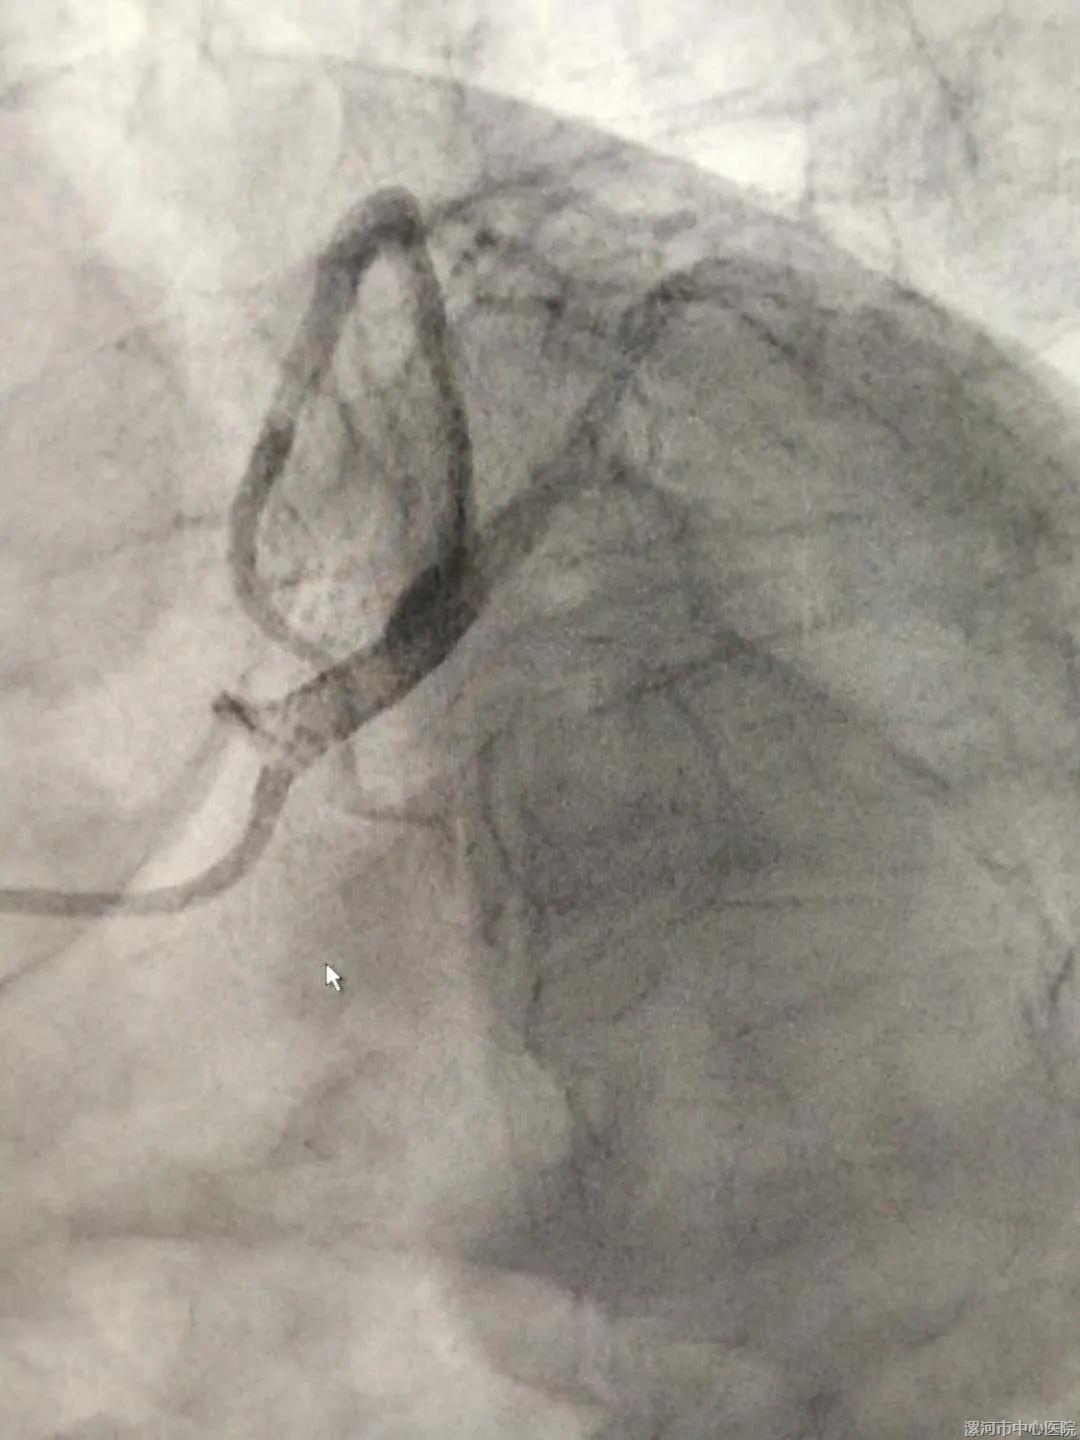

②术后

14点1分,在刘东亮教授的精心指导下,全体手术医师、技师、护士通力配合,导丝顺利通过左主干闭塞处,成功开通急性闭塞的血管,于左主干植入1枚支架,行血管内超声检查提示左主干支架贴壁膨胀良好。经过积极的抢救,老先生的心率、血压平稳下来了,冠状动脉内血流逐渐恢复正常,生命体征趋于稳定,随即返回CCU病房密切监护治疗。